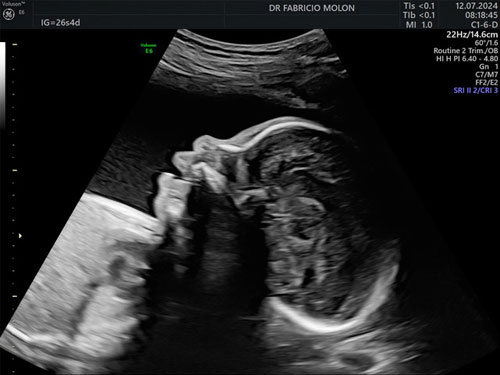

US morfológica do 2º trimestre

Um exame detalhado importante para verificar a saúde do feto e o andamento da gestação.

É realizada entre 20 e 24 semanas.

Algumas questões que vamos avaliar neste exame:

• Possíveis malformações;

• Possíveis anomalias genética;

• Avaliação geral da placenta, líquido amniótico e colo uterino.